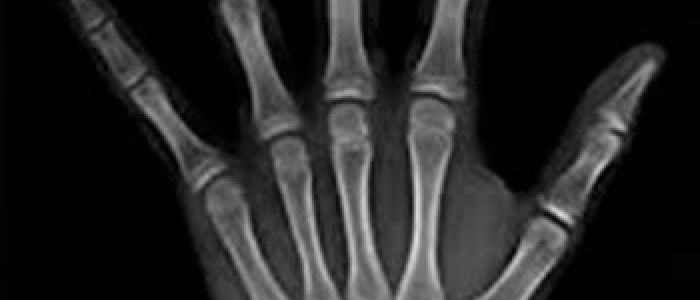

Radiografías Extraorales

Las radiografías extraorales se emplean cuando no es factible obtener información diagnóstica adecuada en las series de radiografías intraorales, es así que son utilizadas para observar un área grande de los maxilares y del cráneo en una sola radiografía. Los exámenes radiográficos extrabucales tienen el propósito de evaluar áreas grandes del cráneo, dientes impactados y patrones de erupción, crecimiento y desarrollo; examinar la extensión de lesiones grandes, traumatismos, articulación temporomandibular. Son de mucha utilidad principalmente en Ortodoncia y Cirugía Bucal.

Existen varias radiografías extraorales entre las cuales se tiene: